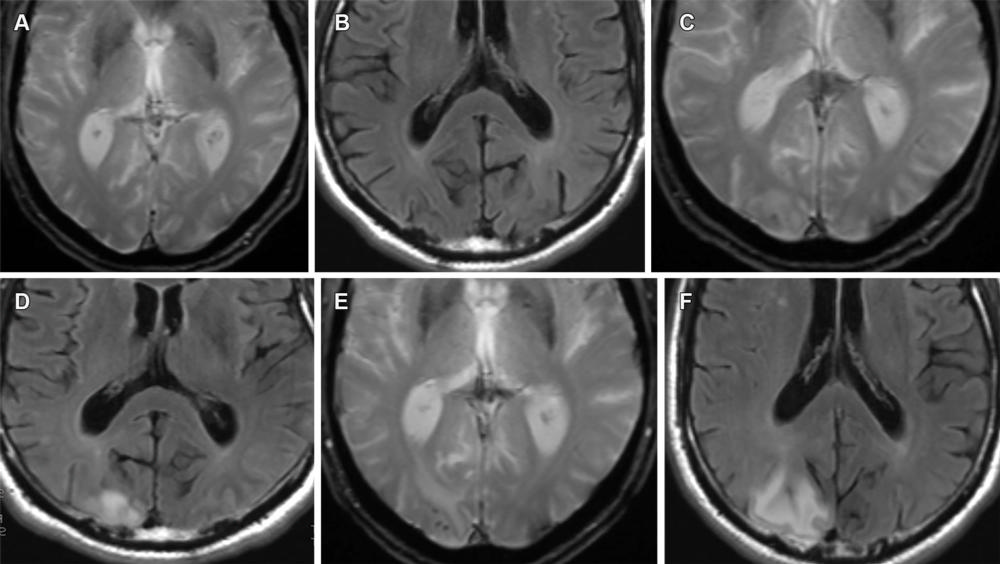

Figure 13. Mild ARIA-E (edema) and ARIA-H (microhemorrhage) in a 62-year-old woman with no clinical symptoms receiving aducanumab therapy. Sequential T2*-weighted GRE image and FLAIR MR images, respectively, are unremarkable at baseline (A, B), show solitary microhemorrhage and mild edema at 4 weeks (C, D), and show progression of edema and microhemorrhages after 8 weeks (E, F). Although the edema is usually reversible, the microhemorrhages persist, as is seen on the follow-up MR images in this case. Edema and microhemorrhages can frequently coexist (ARIA-E+H) and are graded separately, with the therapy decision based on the highest grade of severity.

High-res (TIF) version